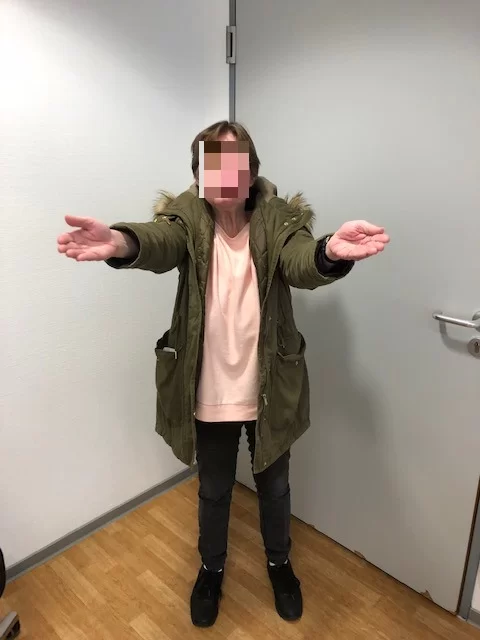

Η ασθενής ανάρρωσε άμεσα και πλήρως, χωρίς νευρολογικό έλλειμα και εξήλθε του νοσοκομείου την 7η μετεγχειρητική ημέρα.

Η μετεγχειρητική εικόνα της ασθενούς ήταν εξαιρετική, χωρίς κανένα νευρολογικό έλλειμα από τις εγκεφαλικές συζυγίες (εγκεφαλικά νεύρα) παρά τη θέση και την έκταση του μηνιγγιώματος.

(Αναπαραγωγή εικόνων με την άδεια της ασθενούς)